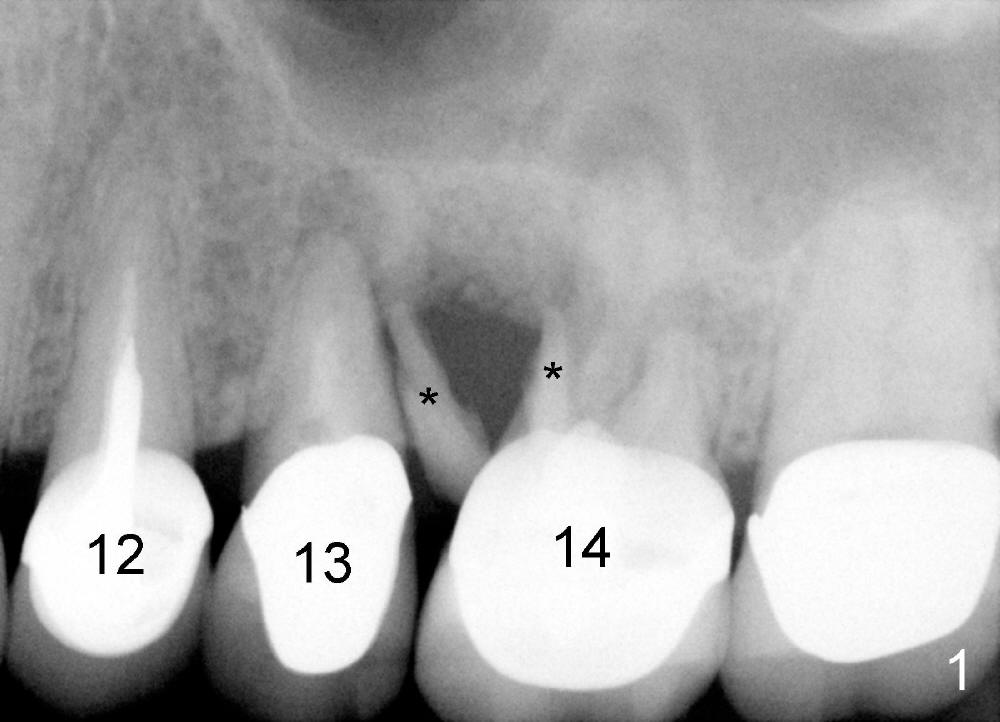

吴先生从小牙齿不好,挺能理解人,所以我们关系还能维持七八年。第一次他来时,我们诊所刚开张,没有多少病人,他左上第一磨牙近中根纵裂(图一:14**),花时间做根切(root amputation,切除近中根近中游离部分),其余两个根做根管治疗(图二)。不久以后他一直有轻微前臼齿区不适,好像第二前臼齿根管治疗充填不佳(图二<),根尖有阴影,不妨重做根管治疗(图三R),之后问题没有解决,根尖切除后,还是好好坏坏,那么再做一次根管治疗(图四R)。好不容易等到他认为疼痛来自于第一前臼齿:颊侧根充填不到位(图四箭头),鄂侧根好像有个牙桩(其实是银汞拴(Amalgam plug)),好像没有根充。这没有什么了不起:除去牙冠,牙桩,重做根管治疗,我们样样都能做。鄂侧根管很快搞通,但是颊侧根管根尖1-2 mm 阻塞,无可奈何。根充(30/.06 for L, 55 for P)后,插入两个三号Coltene Whaledent stainless steel posts以及做牙冠。每当他回来洗牙,汇报前臼齿区仍有不适,不知那颗牙齿有毛病时,对颊侧根管处理不当深感内疚,问题真得出于那里吗?